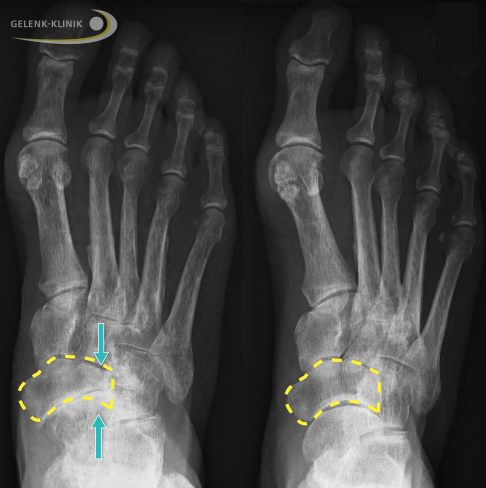

Vergleich eines gesunden Talonavikulargelenks mit einer Osteonekrose des Kahnbeins bei Müller-Weiss-Syndrom. Das vordere untere Sprunggelenk zwischen Kahnbein (Os naviculare) und Sprungbein (Talus) ist unmittelbar mitbetroffen. © Gelenk-Klinik

Die Röntgenaufnahmen zeigen bei fortgeschrittenem Müller-Weiss-Syndrom ein abgeflachtes Kahnbein, dass zunehmend nach innen (medial) und Richtung Fußrücken (dorsal) verdrängt wird. Das Kahnbein kann wie ein Komma erscheinen. Durch den Umbau (Sklerosierung) des abgestorbenen Knochenbereichs erscheint das Kahnbein auf der Röntgenaufnahme deutlich dichter und kompakter. In frühen Stadien der Erkrankung ist die Röntgenuntersuchung nicht hilfreich, da die knöchernen Veränderungen noch nicht sichtbar sind.

Erscheinungsform des Müller-Weiss-Syndroms: Sklerosierung des Kahnbeins und Ausbildung einer Komma-Form und Verlagerung des Kahnbeins zum Fußrücken aus seiner normalen Position (dorsalseitige Subluxation). © Gelenk-Klinik